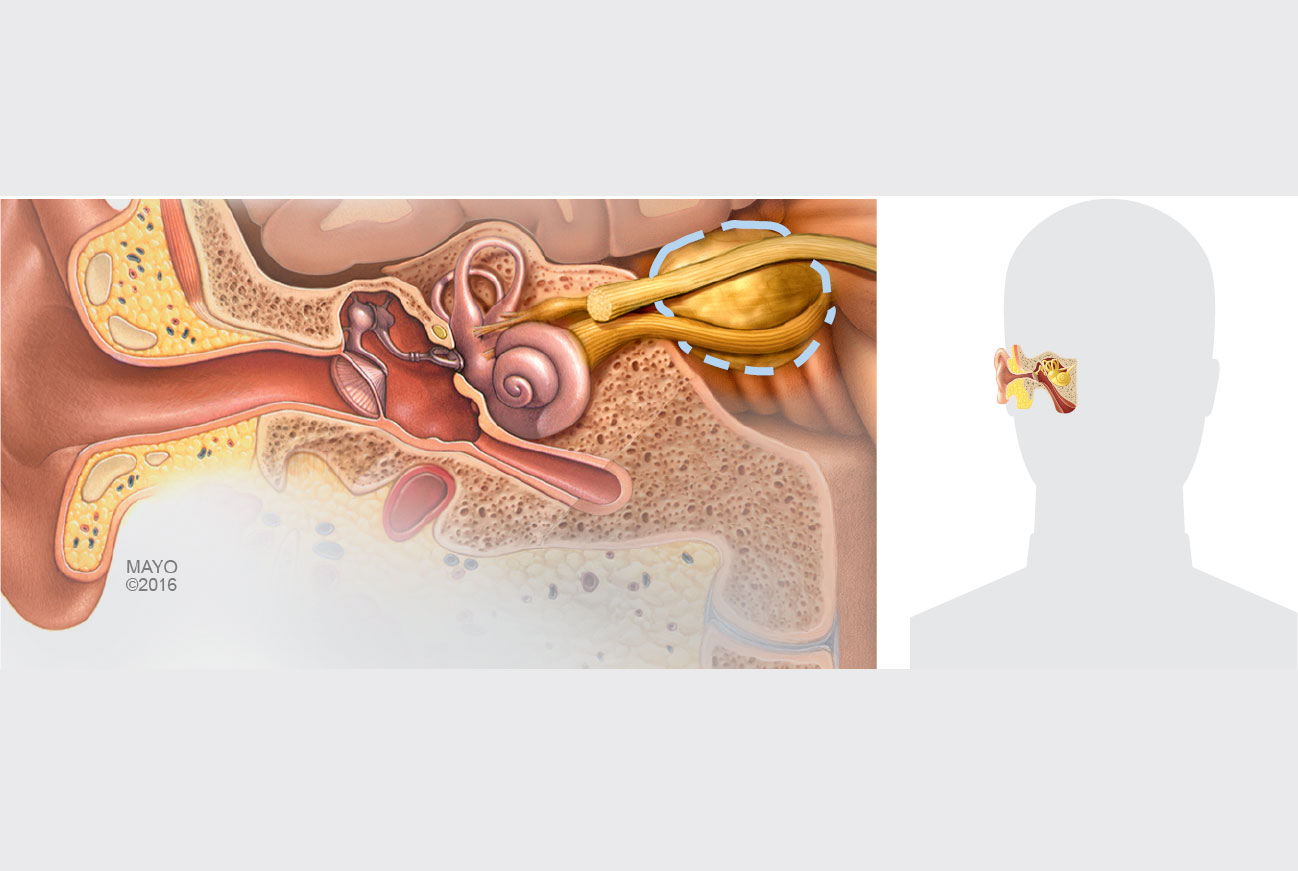

Modell som viser svulst på balansegangen, tverrsnitt av øregang, og plassering i hodet på menneskesilhuett.

Illustrasjon: ©Mayo Clinic 2016